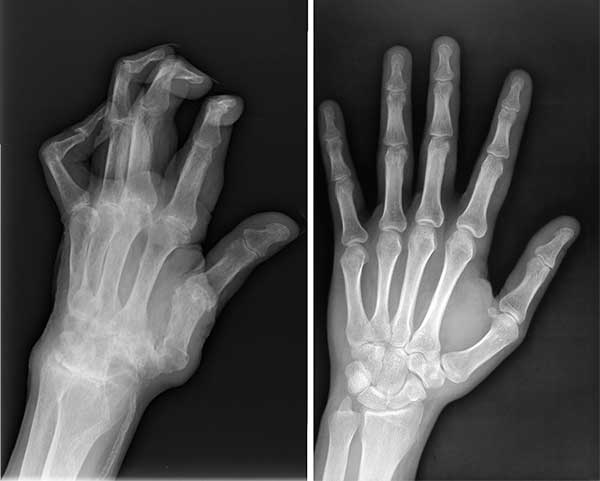

राजेश के जोड़ो की तस्वीरें देखें, जब मैंने उसे उपचार देने से पहले देखा था:

📌यहां स्पष्ट रूप से देखा जा सकता है कि नमक ने गलत उपचार के कारण जोड़ को पूरी तरह से नष्ट कर दिया।

यहां स्पष्ट रूप से देखा जा सकता है कि नमक ने गलत उपचार के कारण जोड़ को पूरी तरह से नष्ट कर दिया। कुछ ही समय में, बड़े टुकड़े ओर्थोसोले को आसानी से हड्डी का बड़ा हिस्सा तोड़ सकते थे, जिससे राजेश को जोड़ के पूरी तरह से खराब होने और स्थायी विकलांगता का सामना करना पड़ता।

📌 राजेश के हाथों की स्थिति, इलाज से पहले और बाद में